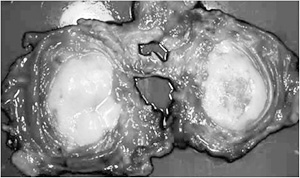

●悪性中皮腫 主に胸膜や腹膜に発生する悪性腫瘍です。ほとんどの場合、アスベストの曝露歴がある人に発症するといわれており、アスベストと関連の深い病気です。患者さんの数は、肺がんと比べて圧倒的に少数です(100分の1以下)。

しかし「クボタ」尼崎工場の周辺住民の被害で、肺がんよりも悪性中皮腫が問題になっているのは、肺がんとくらべてごく少量のアスベスト曝露で発症しやす いためだと思われます。曝露後20~30年ほど経過すると発症者が増え始め、だいたい35年後がピークといわれています。

治療は肺と胸膜をいっしょに取り除く「胸膜肺全摘出術」に加えて放射線療法、化学療法(抗がん剤投与)をおこないます。ただ予後は悪く、横須賀共済病院 の三浦溥太郎医師の調査では、2年生存率29・6%、5年生存率3・7%で、1年以内に半数以上の方が亡くなっています。